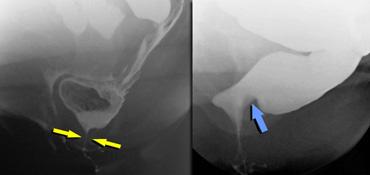

Bên trái là hình vẽ sơ đồ tư thế nghiêng của cơ nâng hậu môn và cơ thắt ngoài hậu môn.

Cơ mu-trực tràng cần ở trạng thái co khi nghỉ (góc hậu môn-trực tràng nhọn).

Trong khi đại tiện, cơ mu-trực tràng cần giãn ra để cho phép phân đi qua.

TRÁI: Cơ thắt tăng trương lực (trong khi đại tiện). PHẢI: Hình ảnh ấn lõm của cơ mu-trực tràng tăng trương lực (không giãn trong khi đại tiện).

Hội chứng sàn chậu co thắt biểu thị tình trạng co cơ sàn chậu kéo dài trong khi đại tiện.

Góc hậu môn-trực tràng (ARA) thường tăng lên khi rặn do cơ mu-trực tràng giãn ra. Mức độ tăng có thể dao động từ 20° đến 40°.

Ở một nhóm nhỏ bệnh nhân có rối loạn tống phân, DRE cho thấy góc hậu môn-trực tràng không thay đổi hoặc giảm khi rặn hoặc đại tiện, những phát hiện này thường do sự ấn lõm của cơ mu-trực tràng tồn tại dai dẳng hoặc nghịch thường.